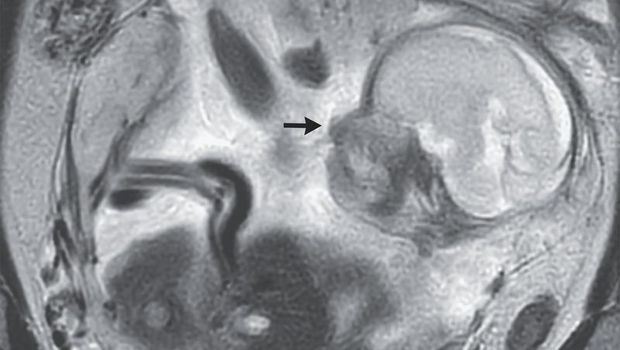

Hasilnya, dokter mendiagnosis wanita tersebut mengalami kehamilan di perut, sejenis kehamilan ektopik atau kehamilan di luar rahim yang terjadi di perut. Bayinya berada di rongga peritoneum atau area tempat organ vital berasa, dengan plasenta yang menempel di bagian atas panggul.

Dokter mengatakan, kasus kehamilan seperti ini sangat langka, dan mungkin terjadi saat janin mulai tumbuh di saluran tuba yang membawa sel telur dari ovarium ke rahim. Seiring waktu, lubang ini bisa pecah sehingga memungkinkan janin 'melarikan diri' ke dalam rongga.

Wanita Ini Ngeluh Sakit Perut-Kembung 10 Hari, Ternyata Ada Bayi di Dekat Ususnya Foto: The New England Journal of Medicine |